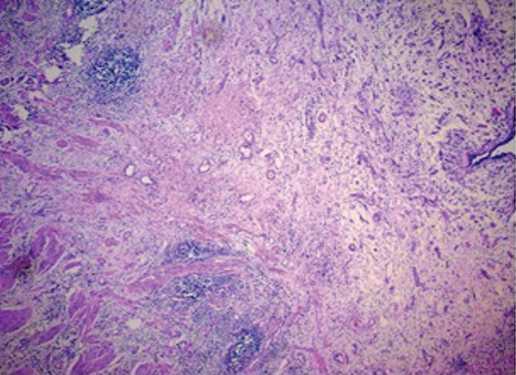

В группе пациентов без стентирования при гистологическом исследовании зоны стриктуры выявлены следующие изменения: гипотрофия (в части препаратов – атрофия) мышечного слоя, при этом отмечена дезорганизация мышечных слоев с нарушением ориентации миоцитов,также прослеживались элементы фиброза в подслизистой оболочке и между мышечными клетками,на срезе сегмент имеет зияющий внутренний просвет в виде «правильной окружности» (рис. 1). В прилежащих отделах мочеточника

Рис. 1. Лоханочно-мочеточниковый сегмент («зона стеноза»), окраска гематоксилином и эозином; х 200

Fig. 1. Pelvic-ureteral segment («stenosis zone»), H&E; x 200